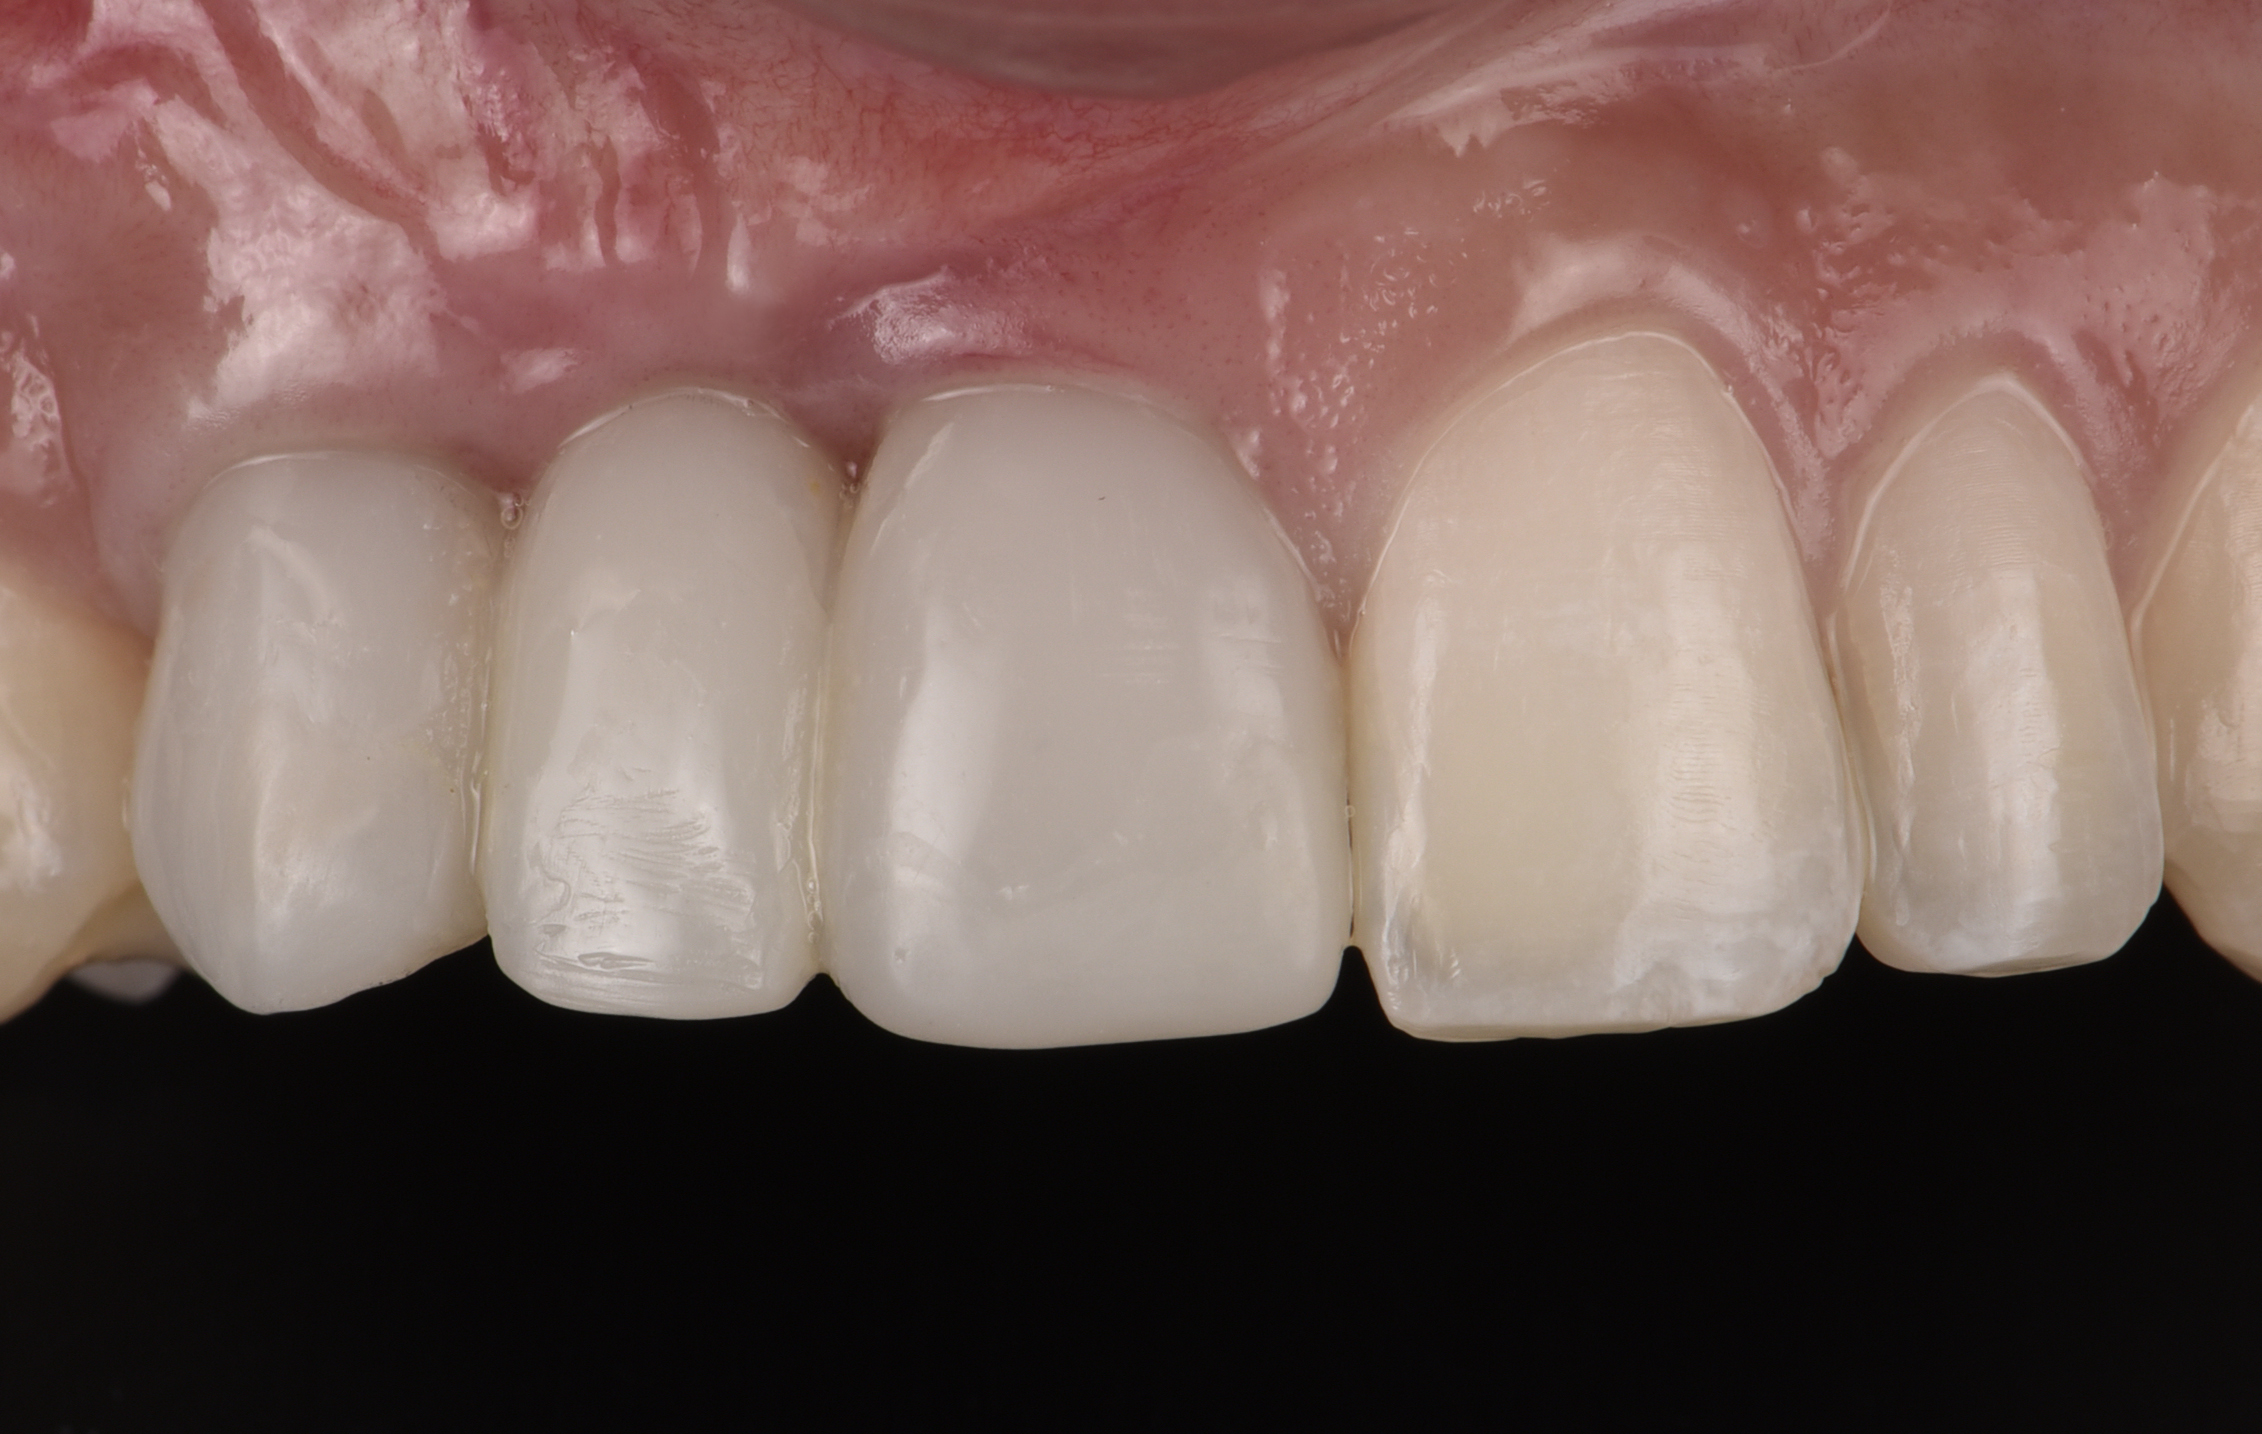

At the patient’s return visit 3 months after implant placement, the composite overlays were removed and the incisal edges of the provisional restoration were modified to approximate the length of the contralateral teeth. The patient reported no complaints, discomfort, or symptomatology throughout the osseointegration period. The implants were stable, and all discernable clinical parameters were within normal limits. The radiographic assessment revealed adequate bone-to-implant contact and osseous crest levels. Similarly, the peri-implant soft tissues displayed a healthy appearance and satisfactory gingival margin architecture (Figure 24 through Figure 27).

Fig 25. Three months post-treatment, peri-implant soft tissues appeared healthy.

Figure 25

Fig 26 . Three months post-treatment, favorable gingival architecture was preserved.

Figure 26

Fig 27. Three months post-treatment, favorable gingival architecture was preserved.

Figure 27